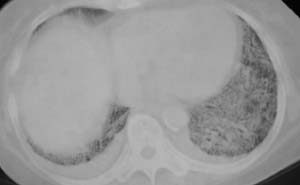

以下是引用liaizhi在2007-7-6 0:05:00的发言:[br]双肺纹理膜糊,沿纹理走行有班点状高密度影。考虑心衰并肺水肿。

以下是引用andymaomao在2007-7-5 22:23:00的发言:[br]双上肺明显,考虑心衰并肺水肿,双侧胸腔少量积液!另不除外肺泡蛋白沉着症及肺泡ca可能。[br]联想机制——心脏病(代偿期)--肺部淤血--后可能并感染致病情加重--抗炎治疗好转,但肺淤血严重,心功能失代偿--心衰而死亡!

以下是引用拾荒者在2007-7-6 13:06:00的发言:[br]支持:心衰,肺水肿及ards